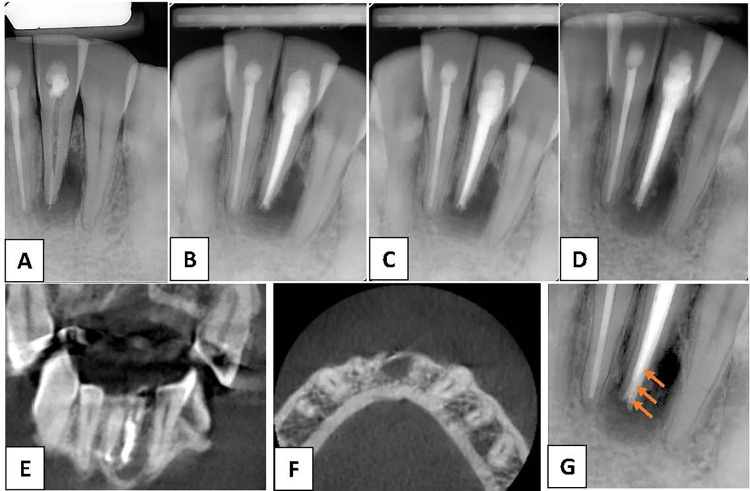

Case presentation: A 42-year-old man presented with persistent sinus tract formation. Despite non-surgical retreatment, the symptoms persisted, and radiographic evaluations, including cone-beam computed tomography, revealed a periapical radiolucency with radiopaque convexities in the apical third of the root. Intentional replantation (IR) was performed to allow direct clinical access for diagnosis and management. Upon extraction, a dark brown, calculus-like deposit firmly attached to the external root surface was observed. After deposit removal, root-end resection and retrograde filling were performed before replantation. Follow-ups at 3 months and 1 year revealed complete healing of the sinus tract and significant radiographic improvements. This case highlights the role of extraradicular biofilms and apical mineralized deposits in persistent periapical inflammation. Sinus tracts may facilitate mineral-ion migration and contribute to the formation of extra-radicular calculi. Mineralized biofilms may not be resolved using orthograde approaches, necessitating surgical intervention.

Conclusion: IR enables thorough inspection and removal of radicular deposits, offering a minimally invasive and successful alternative to conventional apical surgery. The findings in this case are consistent with those in previous studies suggesting the usefulness of IR for managing refractory periapical lesions caused by extraradicular infections or mineralized biofilms.